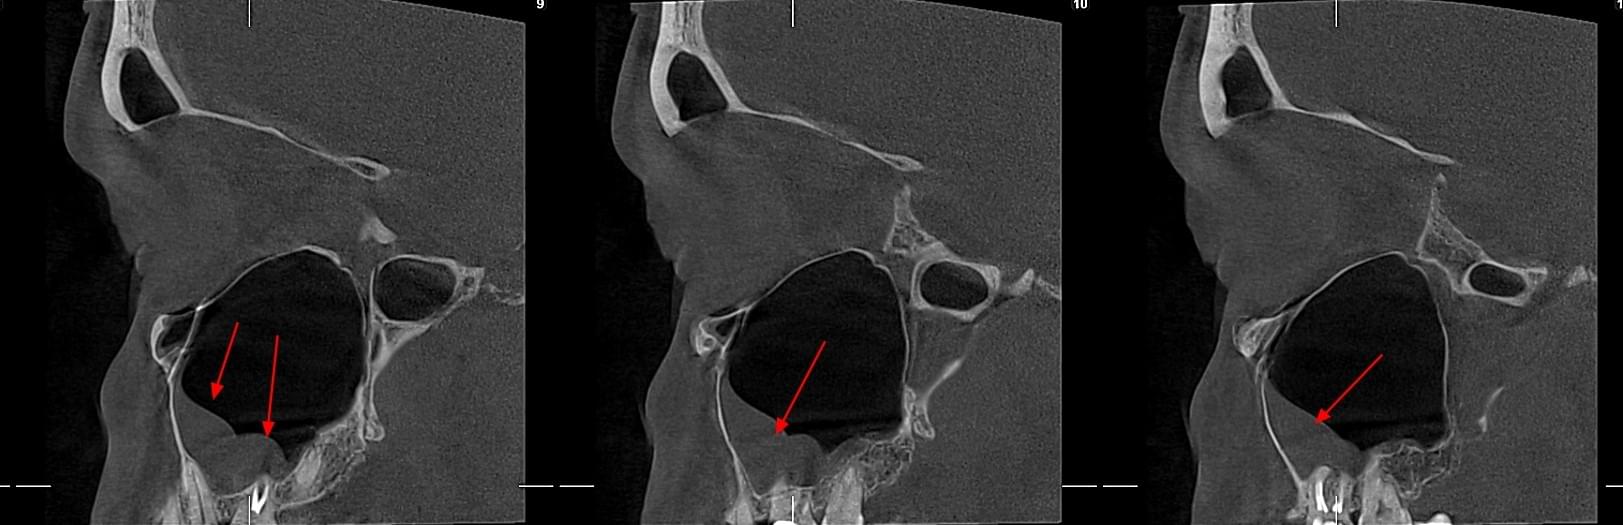

КПКТ (конусно-променева комп’ютерна томографія) — це 3D-знімок високої роздільної здатності. На відміну від звичайного рентгену, КТ показує: